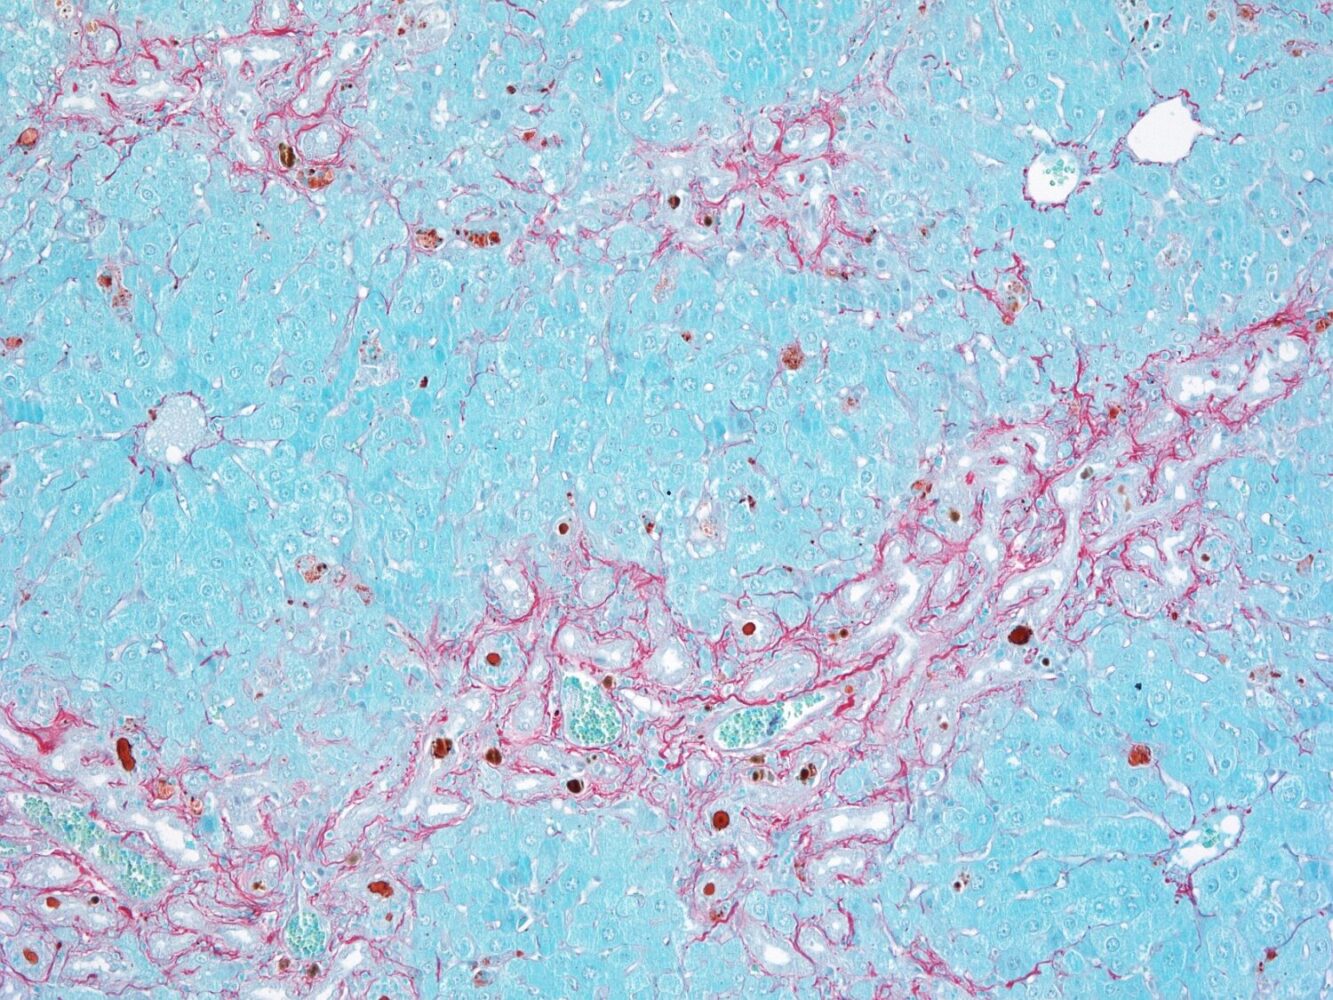

Many liver diseases share a common characteristic: fibrosis, that is, the progressive accumulation of scarring in the liver tissue. Those scars – the liver’s response to persistent injuries or attacks– can prevent the organ from functioning properly. Fibrosis affects millions of people worldwide and is a decisive step in the progression towards cirrhosis, a potentially fatal condition that can develop into liver cancer.

This system is key for the bile ducts to function as an effective barrier. However, in certain diseases or genetic conditions, the FXR protein stops working properly or even being expressed, resulting in BEC cells to lose this control mechanism: they proliferate excessively, the barrier weakens, and bile acids leak into the tissue that performs the liver’s functions—the liver parenchyma.

Upon reaching areas of the liver where they should not be, bile acids activate other cells – stellate cells – which generate scars. If these accumulate, they lead to liver fibrosis. Both excessive proliferation of BEC cells and fibrosis can progress to liver cirrhosis, a serious and potentially fatal disease.